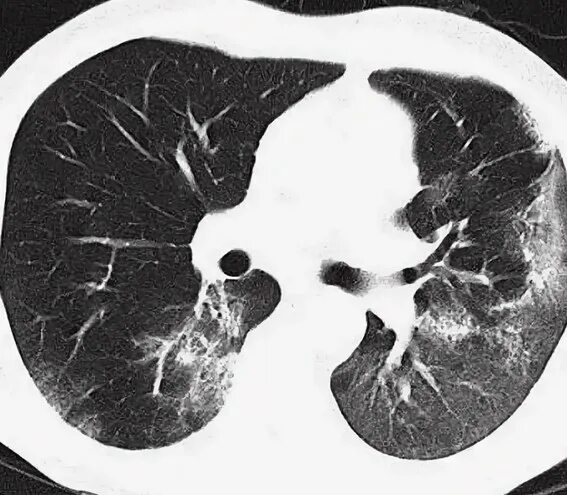

Как выглядит пневмония на кт